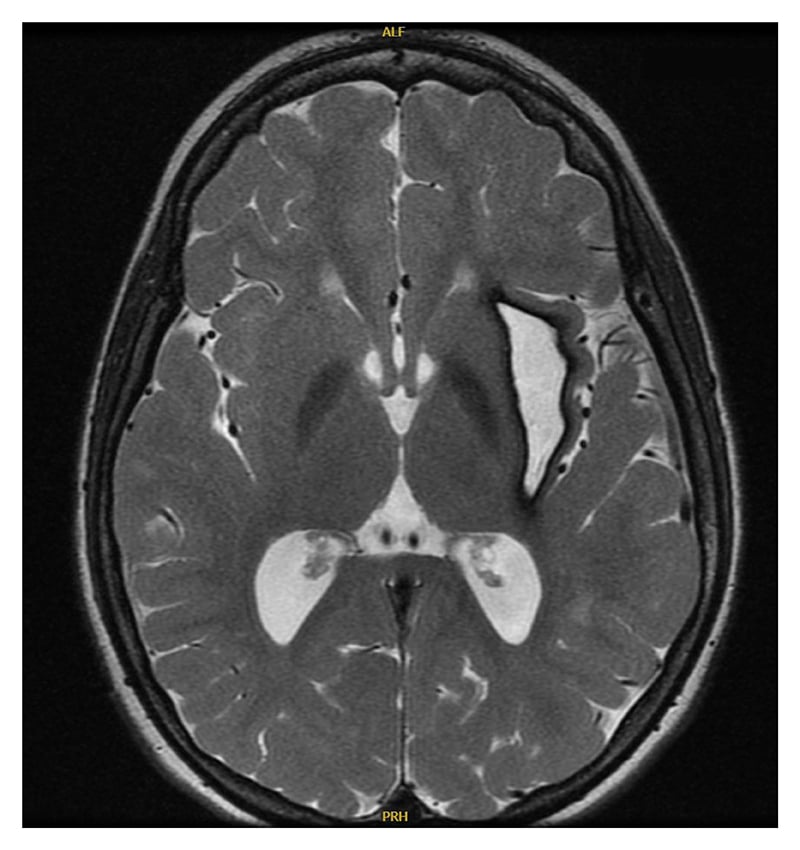

His family history is unremarkable for any autoimmune or autoinflammatory diseases, including interferonopathies. He has older siblings who are healthy. There is no history of parental consanguinity. Additional laboratory workup revealed hypergammaglobulinemia (IgG, 1,960 mg/dL), positive antinuclear antibodies (1:160), and hypothyroidism. Brain MRI and magnetic resonance angiography (MRA) showed new T2 hyperintensities, a chronic hemorrhagic cavity in the left subinsular region (Figure 1), and a right medial cerebral artery (MCA) aneurysm. Serial imaging noted aneurysm progression, and angiography at age 14 years revealed persistence of the right MCA aneurysm and a new aneurysm on the left lenticulostriate artery (Figure 2). Endovascular embolization was unsuccessful, and open craniotomy was deferred due to surgical risk. Repeat MRA at age 16 years showed stable aneurysms.

Figure 1: Brain MRI shows T2 hyperintensities and a chronic hemorrhagic cavity in the left subinsular region.